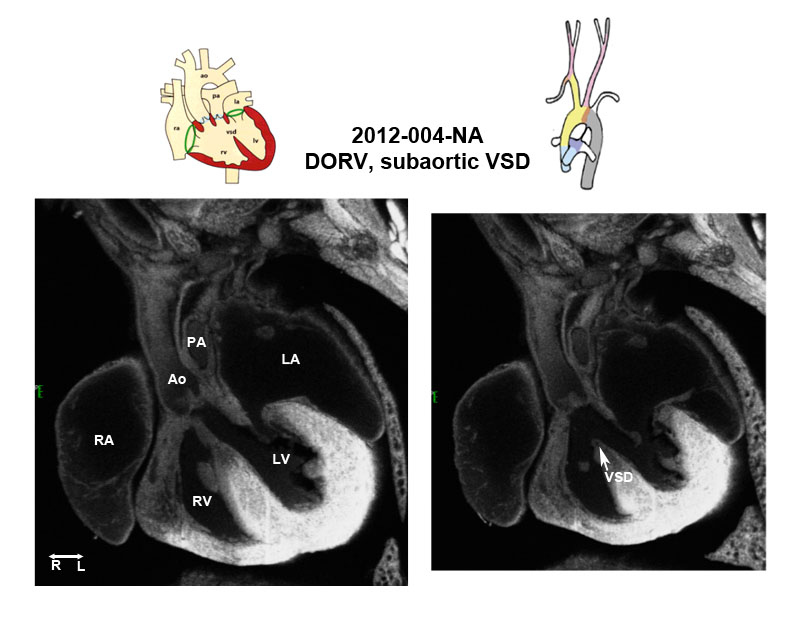

Caption EFIC Summary

Copyright This image is from the Laboratory of Dr. Cecilia Lo, a member of the Cardiovascular Development Consortium (CvDC), Bench to Bassinet (B2B) program of the National Heart Lung and Blood Institute (NHLBI), and is displayed with the permission of the authors. J:175213